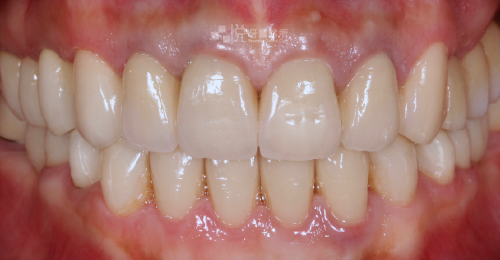

原先有嚴重的牙周病,搭配 4 次的水雷射,約 1 個月的治療時間,就有顯著改善牙周病問題。

舊有假牙侵犯到「生物寬度」(意指假牙邊緣放到牙肉底下太深的位置),導致牙齦有紅腫流血悶痛的發炎反應,本來的牙齒長度偏短、左右牙齦高度不對稱的狀況。

透過【水雷射牙冠增長術】後,讓牙齦恢復健康、和諧的外觀,並完成全口假牙的重建。